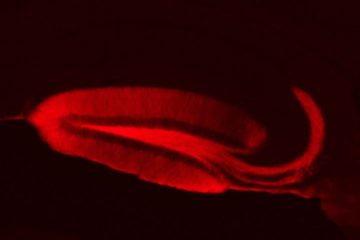

La PS et l’APP sont des protéines abondantes des compartiments présynaptiques, mais leur rôle physiologique y reste un mystère. Partant de l’hypothèse que la PS joue un rôle dans la plasticité présynaptique, les chercheurs ont développé des outils de transfert de gène chez la souris pour combiner la manipulation de gènes « présynaptiques » et la stimulation par une lumière bleue, sélective des synapses mutées (techniques d’optogénétiques combinées à l’électrophysiologie).